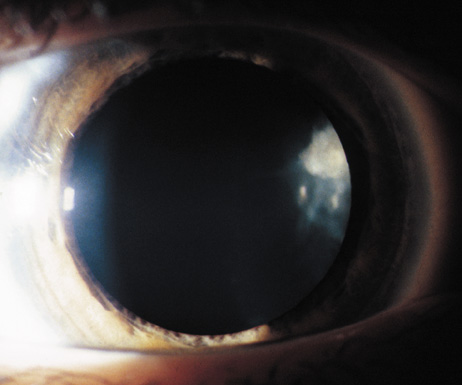

Uveal Tract.

Lisch nodules are hamartomas (a tumor involving only those tissue elements normally found at the involved site) of the iris pigment epithelium. They are dome-shaped discrete lesions, are typically light brown in color, and may also be found in the angle.38 Lisch nodules appear earlier (33% at 2.5 years, 50% at 5 years of age)39 than neurofibromas. They are benign and can help to confirm diagnosis in children who may have café au lait spots as the only other clinical finding. Lisch nodules are present in nearly all adults with NF139,40 but are rare in NF2 (Fig. 3).41,42 Diffuse nodular iris nevi (also known as iris mamillations) should not be confused with Lisch nodules. Its clinical significance is not well established.43,44

- At least two Lisch nodules (Fig. 3)

Cataracts in NF2 were recognized in 1986.97 They are common, reported to be found in 69%,98 81%,91 85%,99 and 87%100of cases. They are typically mild98 and a lens opacity may be the initial manifestation of disease, as found in 10% (5 of 49 patients) in one study.98

Retinal hamartomas affect about 10% to 20% of patients (8% in one study91and 22% in another98) and may be associated with a more severe phenotype of NF2.91,98 Combined pigment epithelial and retinal hamartomas (CPERH) and epiretinal membranes have been reported.101–103 Lisch nodules are rare in NF2. The absence of Lisch nodules, in association with the presence of posterior subcapsular or cortical cataracts (Fig. 8) may aid the differentiation of NF1 and NF2.97,104,105 Optic nerve sheath meningiomas may cause significant visual impairment in the first years of life (Table 2).84,106